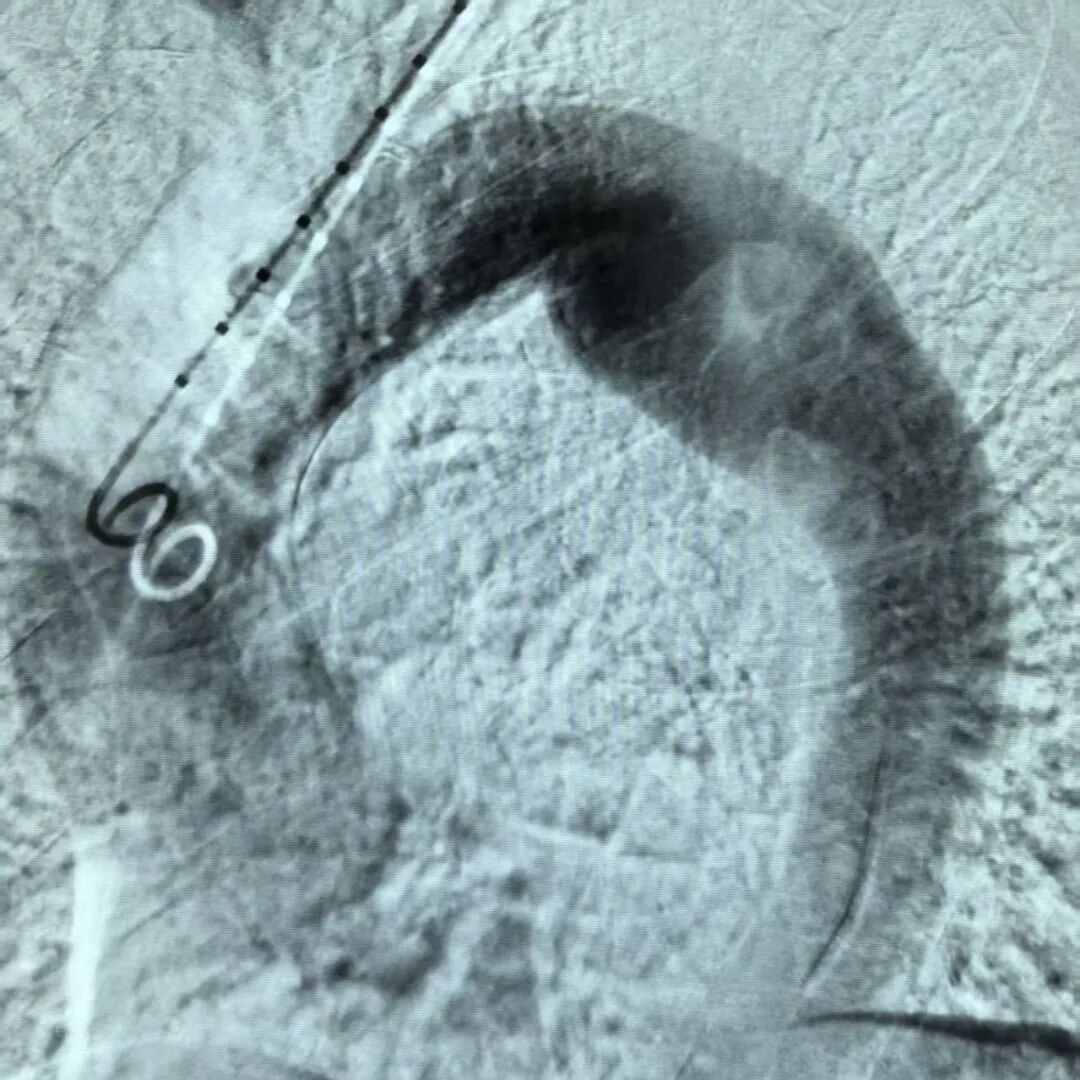

手术当日,杨征团队根据术前CTA及术中综合评估,在数字减影血管造影的实时、高清引导下,沿血管将精心挑选的覆膜支架系统,毫厘不差地释放在病灶预定区域,瞬间隔绝了血流对瘤壁的冲击,并将重要分支血管完美保留。手术仅耗时一小时,出血极少。术后再次造影证实,瘤体被成功隔绝、重要脏器血供完好无损。

STEVAR术后影像

相比于传统开胸手术可能带来的巨大创伤和漫长恢复期,TEVAR手术的微创术式显然更具优势。术后结合中医“益气活血、化痰通络、扶正固本”的治疗原则,以改善气血运行、稳定瘤体为本,中西医结合共同调制。复查CTA显示,支架位置完美,瘤体隔绝完全,主动脉形态恢复正常。一周后,陈先生康复良好,顺利出院,踏上了回家的路途。